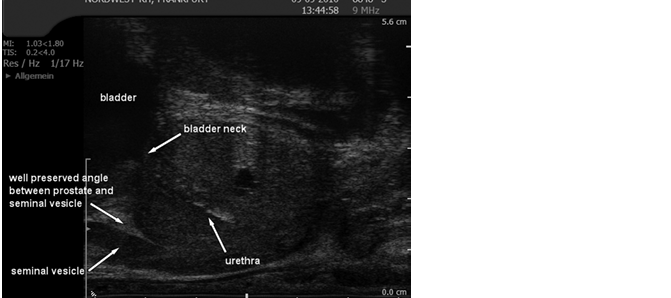

4.4 Prostatic urethra

The prostatic urethra runs through the prostate from the base of the bladder to the apex of the prostate. It is a midline structure unless there is asymmetric glandular enlargement. There is a triangulated portion at the verumontanum where the ejaculatory ducts drain into the urethra. There is a variable amount of smooth muscle around the urethra and this, with the urogenital margin, accounts for its visibility on ultrasound in the collapsed state.

Fig. 7. Ultrasound of the gross anatomy of the prostate demonstrated on TRUS

(Courtesy: S. Hieronymi)

4.5 Seminal vesicles and ejaculatory ducts

The seminal vesicles are paired sac-like structures of variable size and shape and lie just posterior and superior to the base of the prostate. A minor degree of asymmetry is common. The paired ejaculatory ducts formed by the union of the vas deferens and the seminal vesicles run through the prostate in the central zone. They communicate with the prostatic urethra at the verumontanum. [13–15] See Fig. 7, section 4.4.